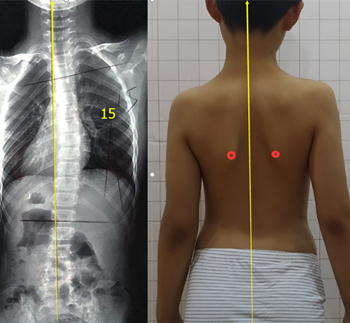

青少年脊柱側(cè)彎一旦被家長發(fā)現(xiàn),應(yīng)積極治療,阻止側(cè)彎進一步加重。但也有一些孩子,在發(fā)現(xiàn)脊柱側(cè)彎后,由于醫(yī)生判斷失誤,家長不重視等等原因,沒有采取任何治療。發(fā)育期的孩子明顯增加較快,每個月基本增加1度。每年12度左右。

盡早展開學(xué)校脊柱側(cè)彎篩查,在30度以內(nèi)發(fā)現(xiàn),最后可以治療到低于20度。如果這樣,對孩子的影響幾乎可以忽略。